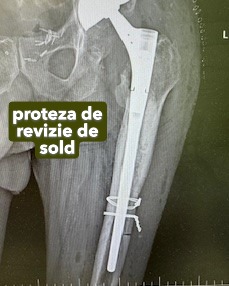

Coxatroza

Este artroza situată la nivelul șoldului. Poate fi unilaterală sau poate afecta simultan ambele șolduri, în diferite stadii.

Pacientul acuză durere și limitarea progresivă a mobilității șoldului. În stadiile avansate, dacă afecțiunea nu este bilaterală, poate apărea o inegalitate a membrelor inferioare.

În stadiile avansate, tratamentul este chirurgical – se efectuează artroplastia totală de șold.

Endoprotezele de șold pot fi:

• cimentate,

• necimentate,

• hibride.

Endoprotezele totale cimentate se implantează la persoanele vârstnice, cu osteoporoză, la care articulația nu poate menține proteza fixată prin presiune și care necesită cimentarea componentelor.

Galerie imagini cu proteze șold și genunchi tratate de dr. Chitea Claudiu Daniel